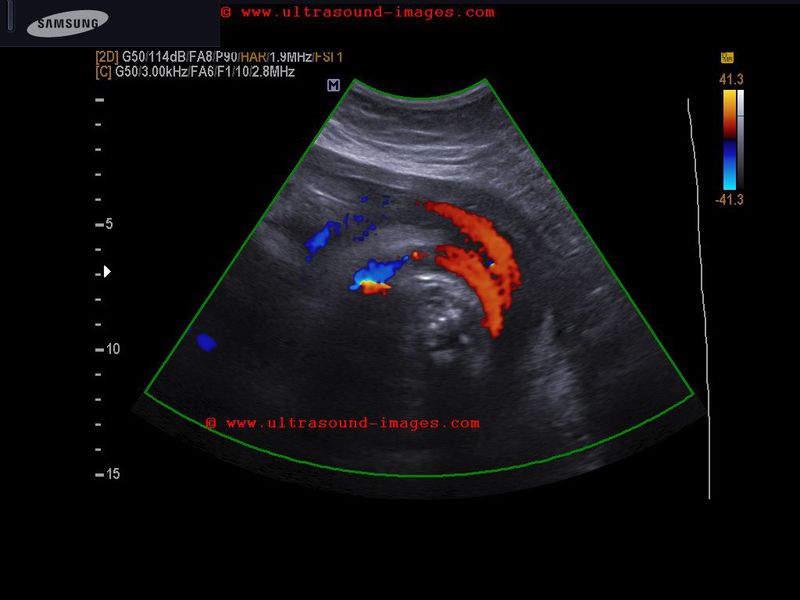

Case-2: hypocoiling of umbilical cord

This is yet another case of hypocoiled umbilical cord. The color Doppler image above shows an almost straight cord. The umbilical cord coiling index is calculated by the total length of the cord in centimeters divided by the total number of coils in the cord. Another method of calculating the umbilical coiling index is: 1/ distance in centimeters between a pair of coils (intercoil distance) of the cord. The normal umbilical coiling index varies from 0.19 to 0.21(based on studies by Ercal et al). Studies done on Indian pregnancies show normal UCI values ranging from- 0.13 to 0.21. Other studies have found that umbilical coiling index less than the 5th percentile is diagnostic of hypocoiled umbilical cord. This color Doppler ultrasound image is courtesy of Dr. Durr-e-Sabih, Pakistan.

Reference: http://medind.nic.in/jaq/t06/i4/jaqt06i4p315.pdf (free journal article- umbilical cord coiling index)

http://www.sirirajmedj.com/content.php?content_id=2539 (free article on method of umbilical cord coiling index and its use as an indicator of Trisomy 21). This article also has an image demonstrating the method of coiling index measurement.

http://www.hkmj.org/supplements/article_pdfs/hkm0702sp1p44.pdf (free article on umbilical cord morpholog and umbilical coiling index (UCI)).